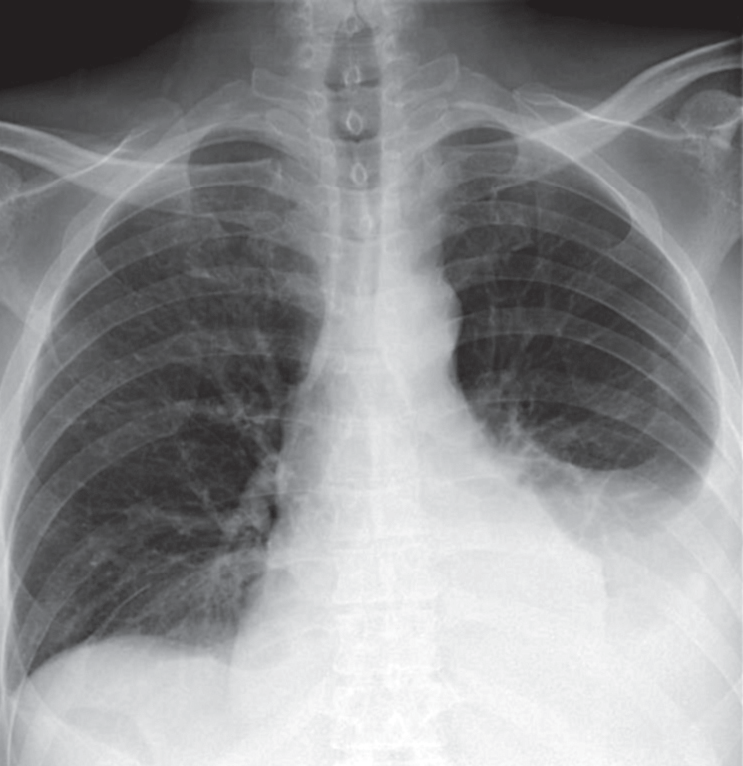

В приемном отделении стационара при осмотре состояние было оценено как тяжелое, выявлен цианоз губ, при аускультации над легкими – везикулярное дыхание, справа в нижних отделах ослаблено, там же выслушиваются мелкопузырчатые хрипы. ЧДД – 20 в минуту. Тоны сердца приглушены, аритмичны. ЧСС – 140 в минуту. АД – 100/60 мм рт. ст. Живот мягкий, безболезненный. Голени пастозны. Выполнена рентгенография грудной клетки, по результатам которой выявлена правосторонняя нижнедолевая пневмония и жидкость в обеих плевральных полостях (рис. 1). На ЭКГ: фибрилляция предсердий с ЧСЖ 120–200 в минуту. Неполная блокада ПНПГ, синдром sI-qIII.

Рис. 1. Рентгенограмма пациента Г. при поступлении в стационар